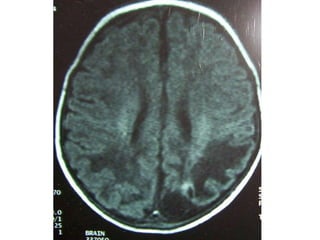

Hypoglycemic brain injury

Determinants-

1.clinical presentation

2.severity of hypoglycemia

3.duration of hypoglycemia

4.concomitant disorders

Areas involved-

1.cerebral cortex (parieto-occipital)

2.hippocampus (dentate gyrus)

3.basal ganglia (caudatoputamen)

less involved-cerebellum,brain stem,s.cord

Hypoglycemic brain injury Determinants- 1.clinicalpresentation 2.severity of hypoglycemia 3.duration of hypoglycemia 4.concomitant disorders Areas involved- 1.cerebral cortex (parieto-occipital) 2.hippocampus (dentate gyrus) 3.basal ganglia (caudatoputamen) less involved-cerebellum,brain stem,s.cord